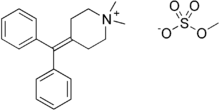

| Formula | C21H27NO4S |

| Molar mass | 389.51 g·mol−1 |

In the field of pharmacology, diphemanil metilsulfate also known as diphemanil methylsulfate is an antimuscarinic (an agent that blocks the action of the natural neurotransmitter acetylcholine).[1]